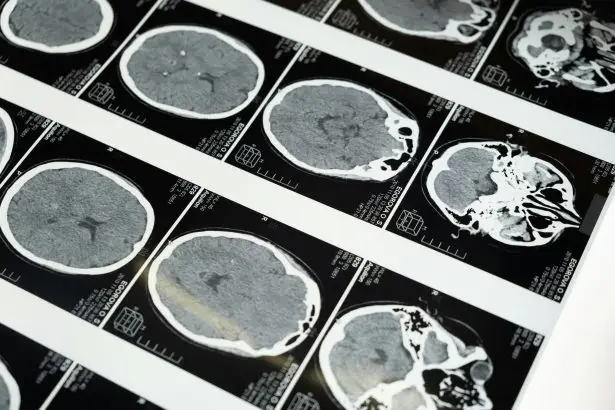

Types of Brain Injuries

From mild concussion to severe trauma, brain injuries vary widely. This category outlines each type, how it occurs, and what parts of the brain are affected. Understanding these differences helps guide treatment and recovery.

Moderate and Severe Traumatic Brain Injury (TBI)

Learn about moderate and severe traumatic brain injuries — their causes, symptoms, treatment, complications, and recovery outlook.